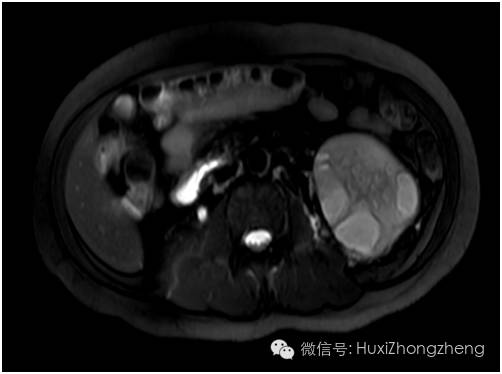

10:00 当我来到MRI室门口时,看见那里早已排起了长队。周末,按常规是不做急诊腹部MRI检查的,我向值班大夫讲明情况后对方愉快地答应给予加做一个急诊腹部MRI。10:40 MRI影像显示患者右肾缩小,左肾多发性囊性病变。

图2 MRI影像显示右肾缩小,左肾多发性囊性病变